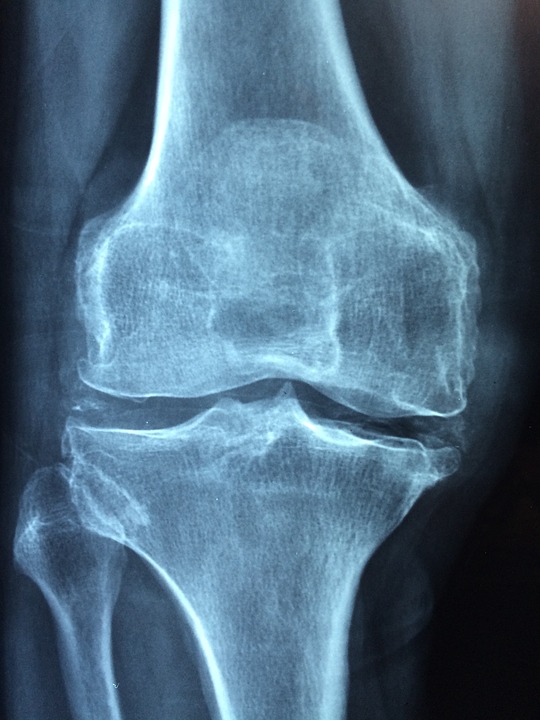

Miasto Suwałki wraz z Akademią Fundacja Aktywnego Rozwoju ma przyjemność zaprosić mieszkańców Suwałk w wieku 30+ na bezpłatne badania densytometryczne osteoporozy oraz bezpłatne badanie słuchu.

Każda diagnozowana osoba otrzyma wynik wraz z informacją o stanie swojego układu kostnego. Po wykonanym badaniu możliwa jest konsultacja z lekarzem reumatologiem.

zdjęcie: pixabay.com